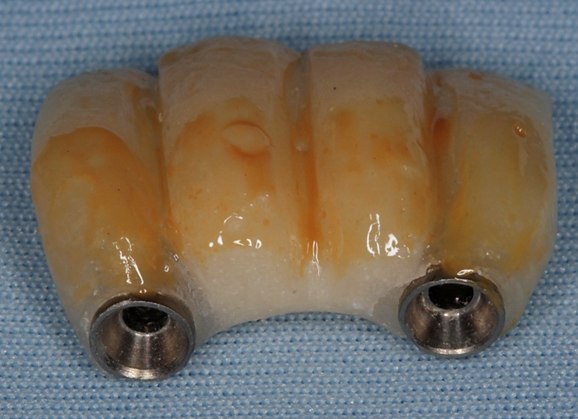

Diante do caso clínico apresentado, constatamos a importância de um correto planejamento, que evidenciou a necessidade de implantes estreitos do tipo Veloce CM e sobre esses implantes os componentes também estreitos do tipo micro-cônico para que os espaços desdentados mésio-distais fossem respeitados de forma adequada.

– em casos de espaço mésio-distal restrito podemos lançar mão de implantes estreitos do tipo Veloce de diâmetro 3.3;

– para seguir a mesma linha de raciocínio, os componentes também devem ter uma plataforma reduzida para poder assentar adequadamente a prótese sobre os implantes e o componente escolhido foi o micro-cônico.